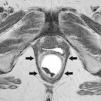

Las secuencias FSE T2 son útiles para evaluar posibles alteraciones musculares, como adelgazamiento o desgarros, en especial del músculo puborrectal (fig. 5). La serie axial debe planificarse en paralelo al propio puborrectal (línea H), desde el ano hasta un nivel superior al sigma. La serie coronal debe planificarse en perpendicular al puborrectal, desde la sínfisis púbica hasta el coxis (fig. 6).